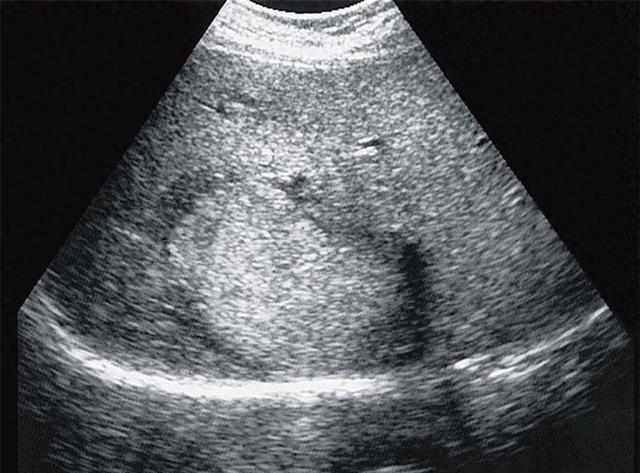

多发巨大肝囊肿一例

图片尺寸2000x1500